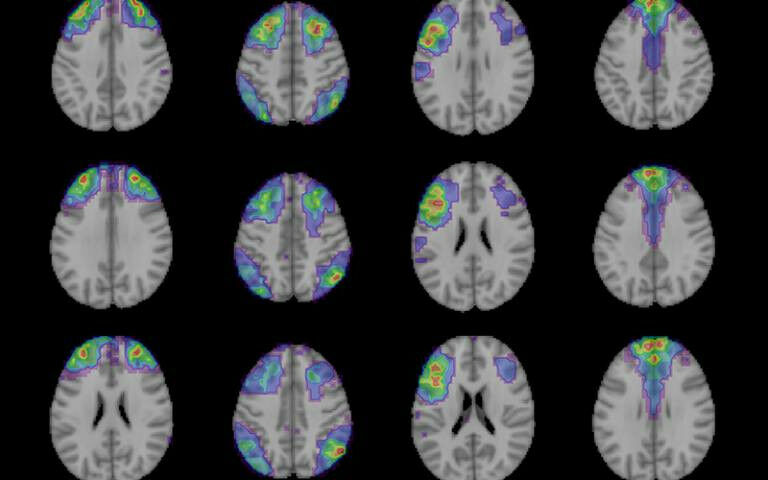

Computational approaches aim to bridge the gap between neuroscience and the phenomena seen in psychiatric disorders by developing models of how the brain works. The models are then linked to behavioural measurements and brain function changes, offering insights into maintaining cognitive function in old age and improving the recognition and treatment of psychiatric disorders.